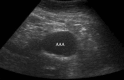

Figure 5

Abdominal aortic aneurysm.